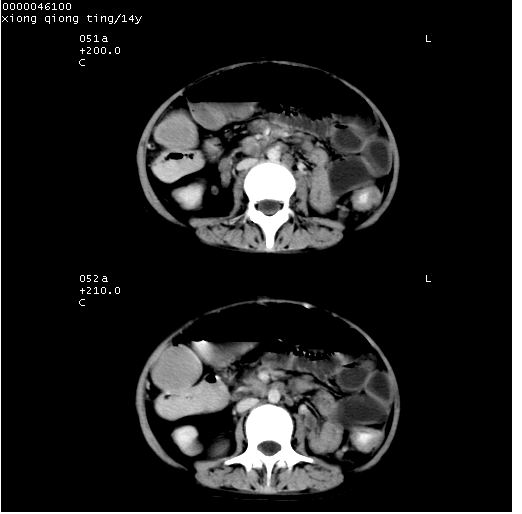

患儿 女,14岁。不规则发热一周,偶感头痛,无抽搐及呕吐。pe:神清,精神差,双侧瞳孔等大等圆,对光反射敏感,双肺未闻及明显啰音,心音有力,腹部触之似揉面感,下腹压痛,无反跳痛。

中下腹及盆腔ct轴位平扫+增强扫描(层厚10mm,螺距1.0,重建间隔10mm),图像如下:

(注:患儿检查当日上午9时口服胃肠道对比剂,下午3时许行ct扫描检查,未行对比剂直肠保留灌肠,检查当日患儿腹泻)

中下腹及盆腔ct轴位扫描(ps+ce)提示:腹部肠管明显充气扩张,并见数个不同宽度之气液平面;疑不全性肠梗阻或肠郁张。临床会诊考虑为患儿腹泻,肠郁张所致;后来未经特殊处理,患儿大便恢复正常,亦无腹胀。